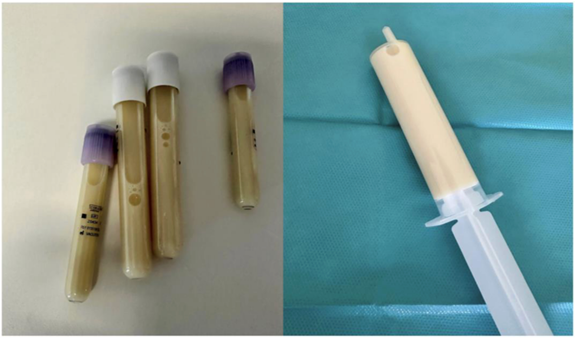

Thoracentesis yielded milky pleural fluid (Figure 2), with 85% mononuclear cells, protein of 5.0 g/dL, LDH of 171 IU/L, glucose of 109 mg/dL, cholesterol of 53 mg/dL, and triglycerides of 1060 mg/dL. Chylomicrons were identified after centrifugation, and the microbiological study was negative. Light's criteria, along with the lipid characteristics, confirmed a bilateral chylothorax compatible with a possible lymphoproliferative syndrome.

Figure 2: Tubes of milky pleural fluid obtained after thoracentesis.